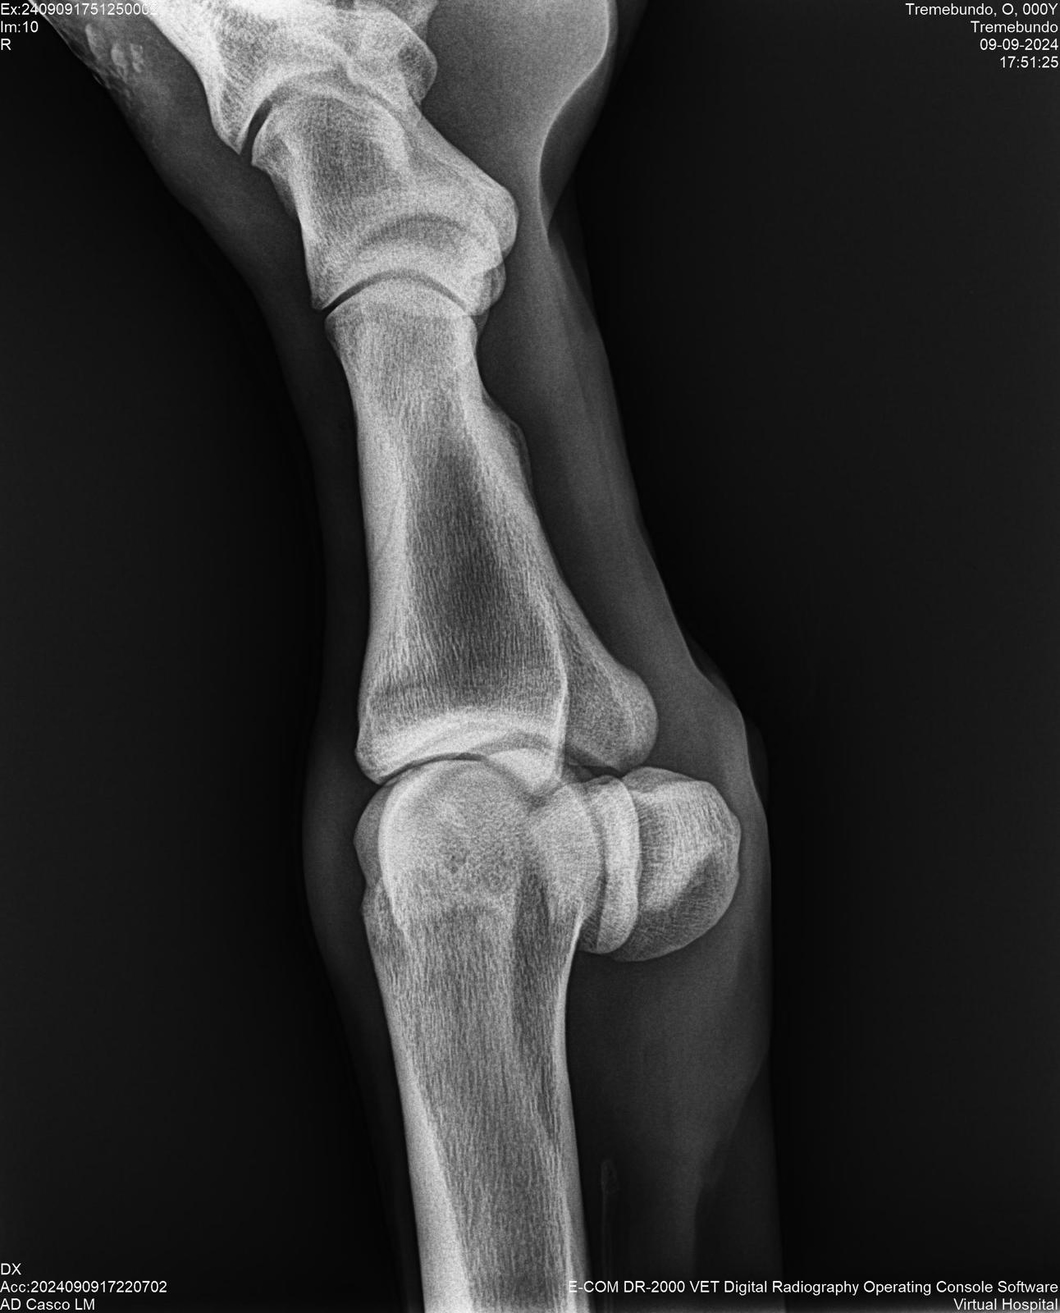

LOTE 37, TREMEBUNDO

Identificador: #291140-

Generacion 2022